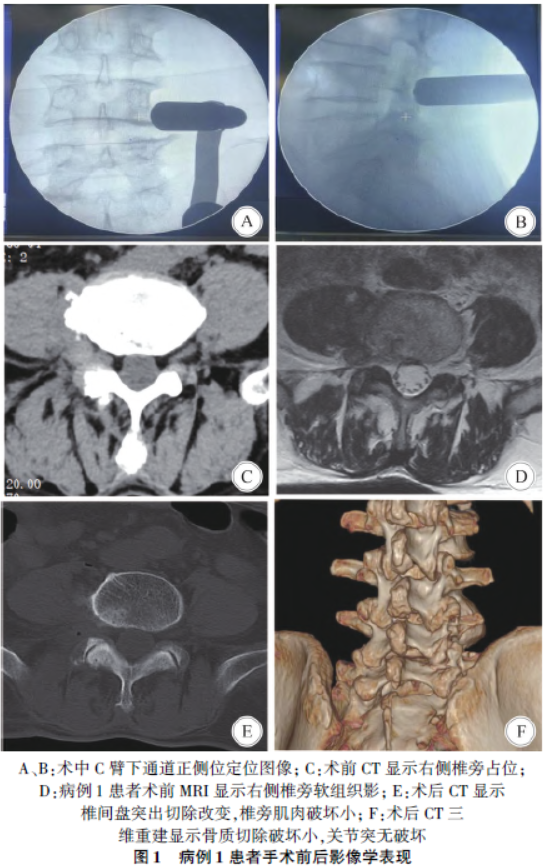

( magnetic resonance imaging,MRI)检查均提示L4/5 椎间孔及(或)外侧存在软组织影,神经根结构及周围脂肪间隙显示不清,均未见明显骨质增生及钙化压迫,其中病例1 椎间孔外侧软组织影一度误认为神经鞘瘤。见图1、图2。

3 例患者均采用气管插管全麻,俯卧位,悬空腹部,术前C 臂正位定位L4/5 节段,中线旁开4 cm 取1. 5 cm切口,止血钳沿关节突关节外上侧钝性分离至横突,不可盲目深入,将内径1. 4 cm 逐级扩张通道置入横突根部,以横突-关节突交界区为骨性标志,经C 臂X 光机正侧位再次确认位置(图1A、B)。显微镜下仔细清除关节突及横突根部软组织,注意保护关节囊,磨除少许横突根部及下关节突关节外侧骨质。

1. 4 术后管理

患者术后第2 天下床活动,尽早鼓励患者行腰背肌锻炼。术后常规复查腰椎CT 三维重建了解关节突关节切除情况,复查腰椎MRI 了解椎间盘切除情况及神经根减压情况。术后3 ~4 日出院,2 周、1 个月、6 个月、1 年门诊或电话随访,采用VAS 评分评估术后症状缓解情况。